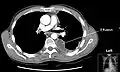

A pleural effusion appears as an area of whiteness on a standard posteroanterior chest X-ray.[12] Normally, the space between the visceral pleura and the parietal pleura cannot be seen. A pleural effusion infiltrates the space between these layers. Because the pleural effusion has a density similar to water, it can be seen on radiographs. Since the effusion has greater density than the rest of the lung, it gravitates towards the lower portions of the pleural cavity. The pleural effusion behaves according to basic fluid dynamics, conforming to the shape of pleural space, which is determined by the lung and chest wall. If the pleural space contains both air and fluid, then an air-fluid level that is horizontal will be present, instead of conforming to the lung space.[13] Chest radiographs in the lateral decubitus position (with the patient lying on the side of the pleural effusion) are more sensitive and can detect as little as 50 mL of fluid. Between 250 and 600mL of fluid must be present before upright chest X-rays can detect a pleural effusion (e.g., blunted costophrenic angles).[14]

Chest computed tomography is more accurate for diagnosis and may be obtained to better characterize the presence, size, and characteristics of a pleural effusion. Lung ultrasound, nearly as accurate as CT and more accurate than chest X-ray, is increasingly being used at the point of care to diagnose pleural effusions, with the advantage that it is a safe, dynamic, and repeatable imaging modality.[15] To increase diagnostic accuracy of detection of pleural effusion sonographically, markers such as boomerang and VIP signs can be utilized.[16]

Massive left-sided pleural effusion (whiteness) in a patient presenting with lung cancer.